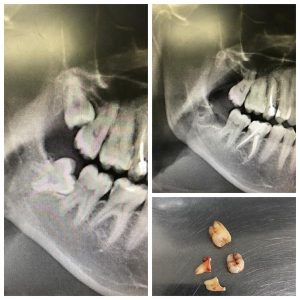

Удаление подобных зубов можно назвать более простым случаем по сравнению с другими, но только лишь в том случае, если у зуба один прямой корень. Тогда удаление может пройти достаточно быстро. Но такие клинические случаи встречаются крайне редко. И, посмотрев на снимок, мы видим крючья, а не корни, которые при должном давлении, могут просто сломаться. Корней обычно 2, и в таком случае нам просто нужно отделить один корень от другого при помощи все того же инструмента — «повышающего» наконечника. И аккуратно каждый из корней достать по отдельности. Начало и завершение удаления таких зубов такое же, как и у всех остальных.

Посмотрите на снимки. Между верхним и нижним — разница в три недели. По ним хорошо заметно, что после удаления зачатков восьмёрок и «разблокировки», седьмые зубы сразу пошли в рост.